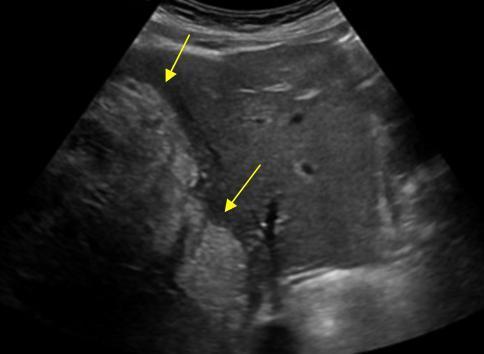

What is Portal venous hypertension?

This is an increase in portal venous pressure (above 10mmHg) or hepatic venous gradient (above 5mmHg).

What is the sonographic appearance of Portal venous hypertension?

Portal vein measures greater than 13mm

Collateral

circulation

Flow reversal

Ascites

Hepatosplenomegaly